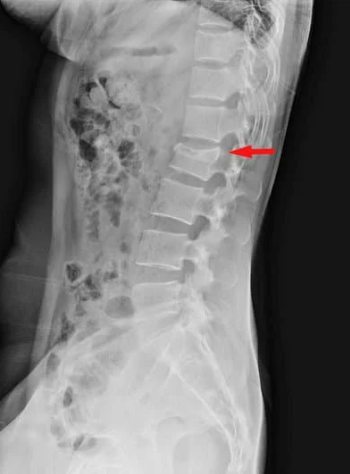

腰椎圧迫骨折は骨粗しょう症を背景にして、転倒などをきっかけに生じる高齢の方に多い病気です。

いつの間にか骨折と言われ、転倒などのきっかけがない場合もあります。

腰の痛みはかなり強く、動けなくなり入院となることもありますので、まずは腰椎圧迫骨折にならないように予防(骨粗しょう症の治療)を行うことが重要になってきます。

診断はレントゲンで行います。

正面と側面を確認し、つぶれている腰骨がないかチェックします。

腰骨がつぶれてなくても安心はできず、不顕性骨折と言ってレントゲンでわからない骨折もあるので、痛みが強い場合はMRIで診断することもあります。

まずは痛みをとるために薬の処方を行い、また腰骨を安定化させるためにコルセットの作成を行います。

また除痛効果のある注射を定期的にうち、痛みを和らげていきます。

骨粗しょう症の治療をしていない方は骨粗しょう症の治療を早期に開始して、再発しないように努めます。

痛みが慢性化しそうな場合は物理療法も並行して行い、痛みが緩和する方向に治療していきます。